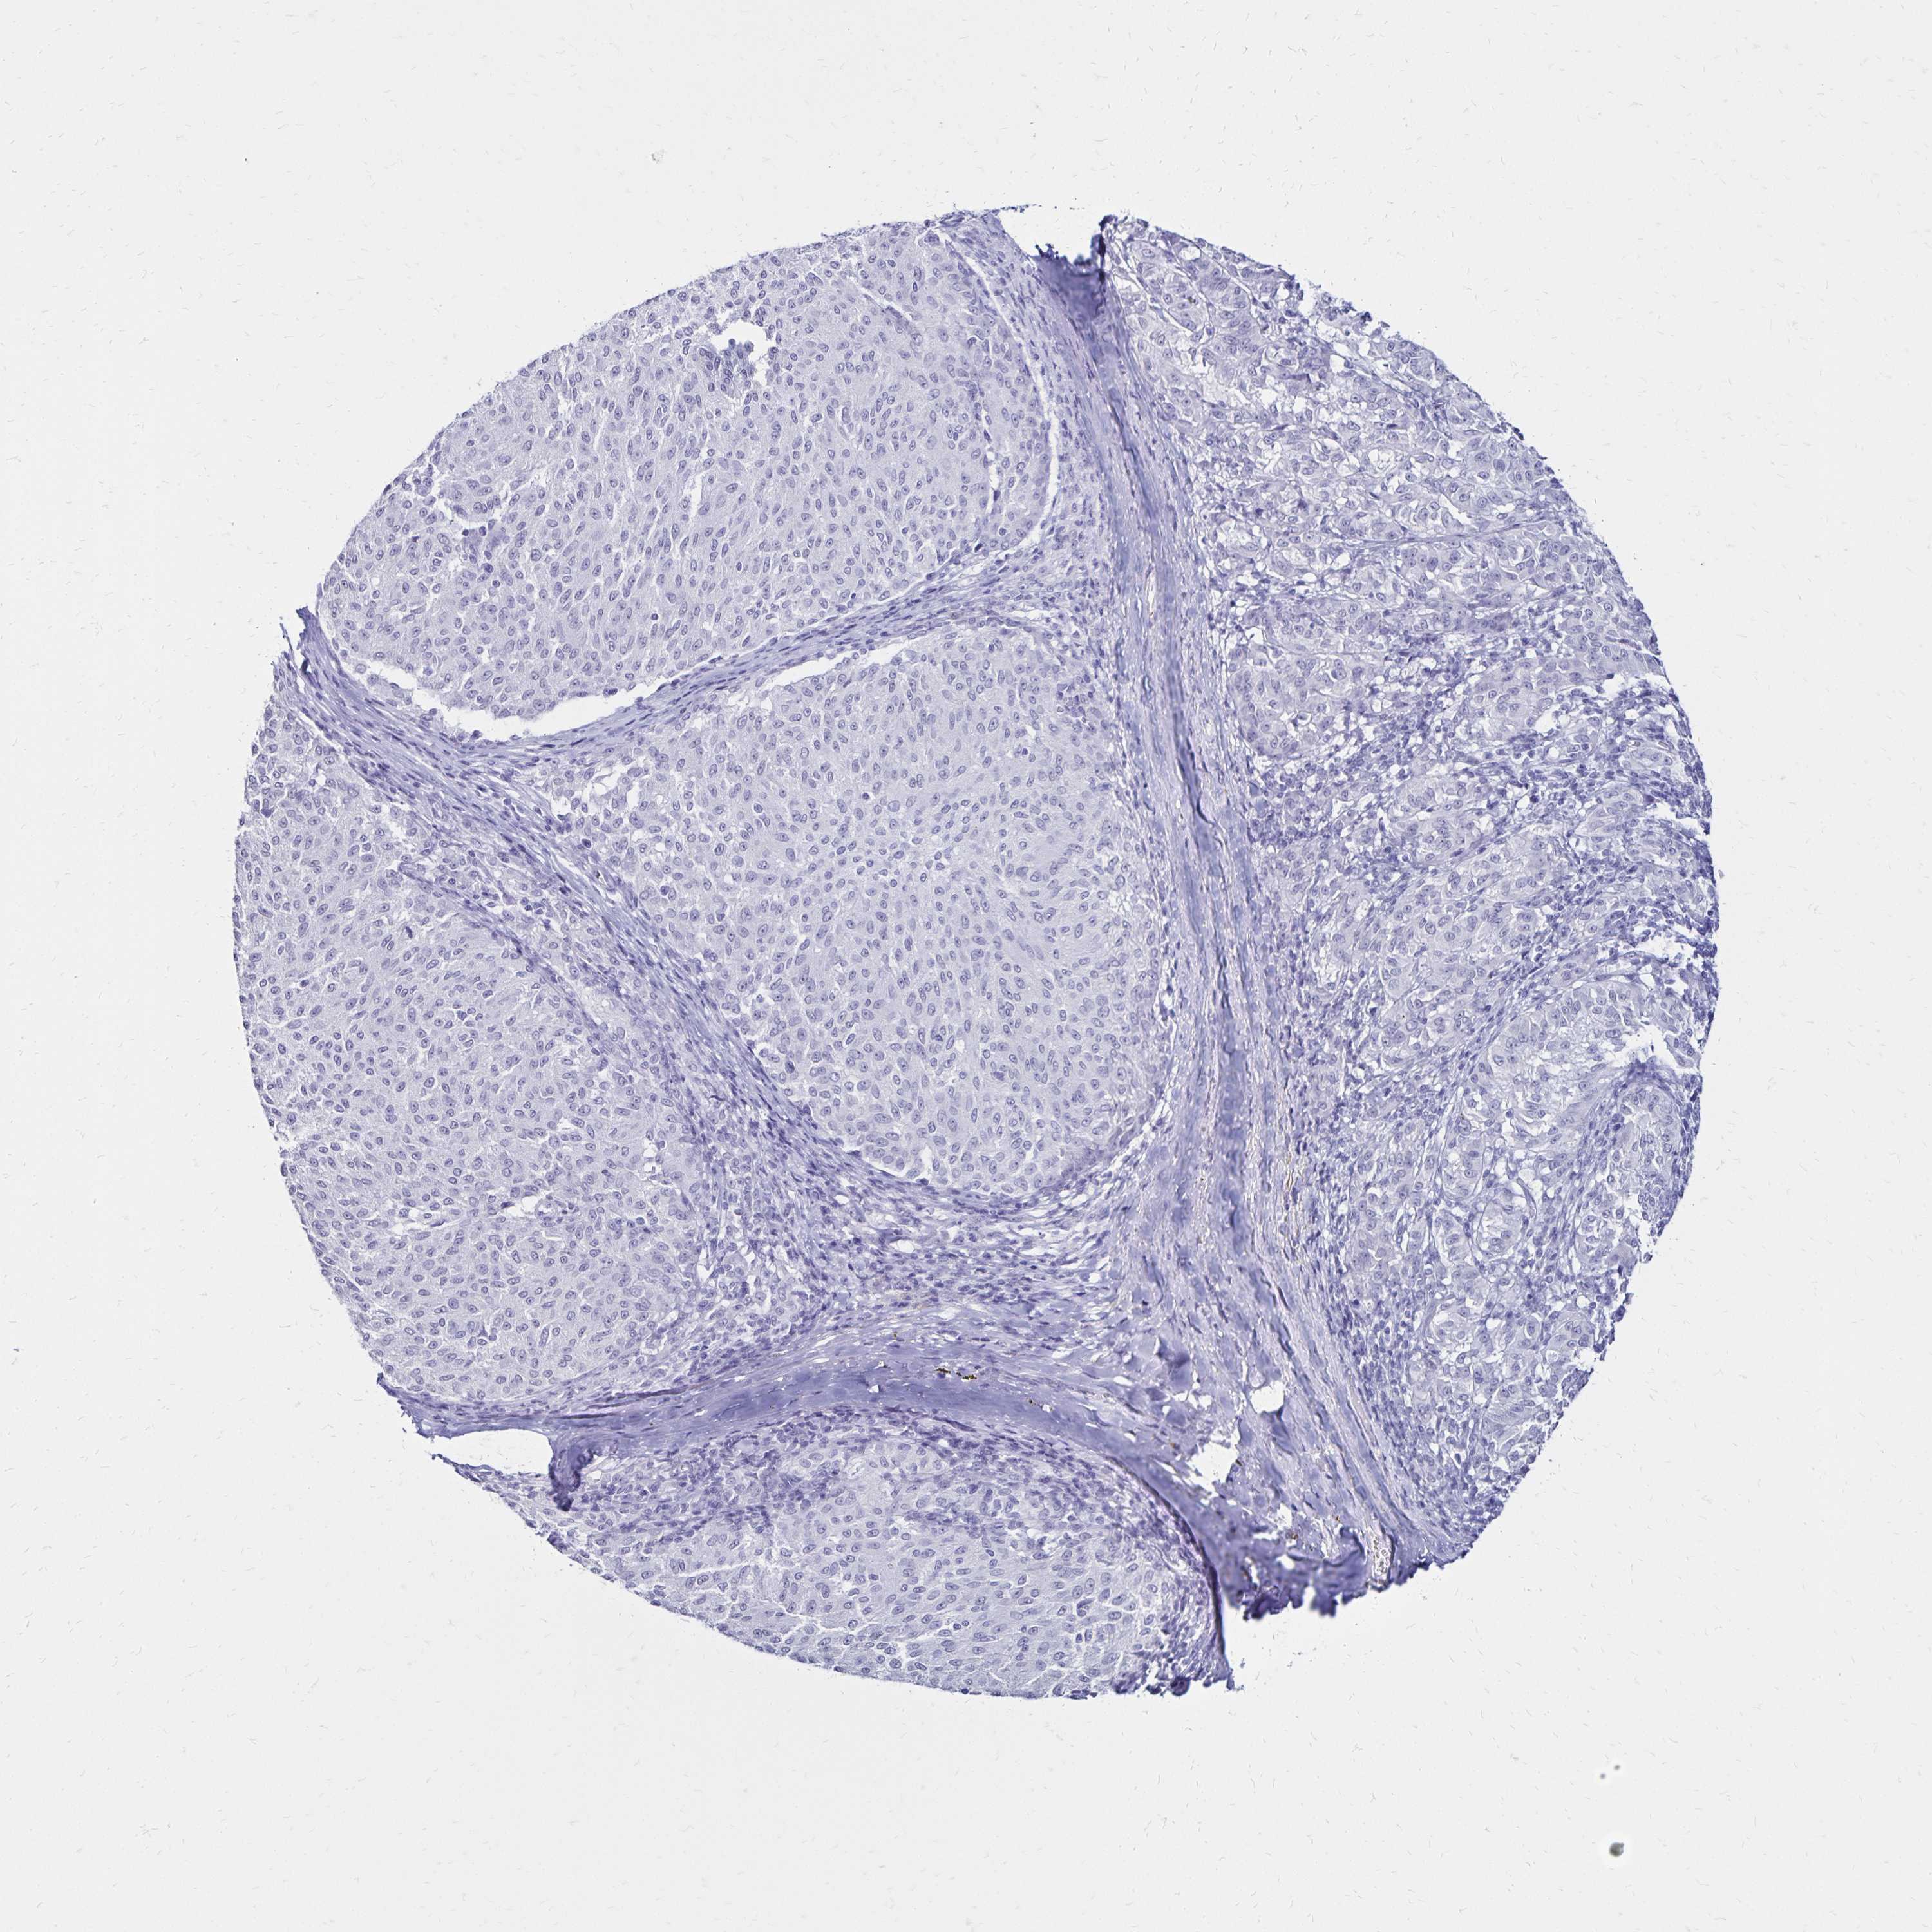

MELANOMA - Protein expressioni

A mouse-over function shows sample information and annotation data. Click on an image to view it in a full screen mode. Samples can be filtered based on level of antibody staining by selecting one or several of the following categories: high, medium, low and not detected. The assay and annotation is described here.

Note that samples used for immunohistochemistry by the Human Protein Atlas do not correspond to samples in the TCGA dataset.

Antibody stainingi

Antibody staining in the annotated cell types in the current human tissue is reported as not detected, low, medium, or high, based on conventional immunohistochemistry profiling in selected tissues. This score is based on the combination of the staining intensity and fraction of stained cells.

Each image is clickable and will lead to virtual microscopy that enables deeper exploration of all samples and also displays staining intensity scores, fraction scores and subcellular localization as well as patient and tissue information for each sample.

Antibody HPA035363

Antibody HPA035364

Malignant melanoma, NOS

Malignant melanoma, Metastatic site